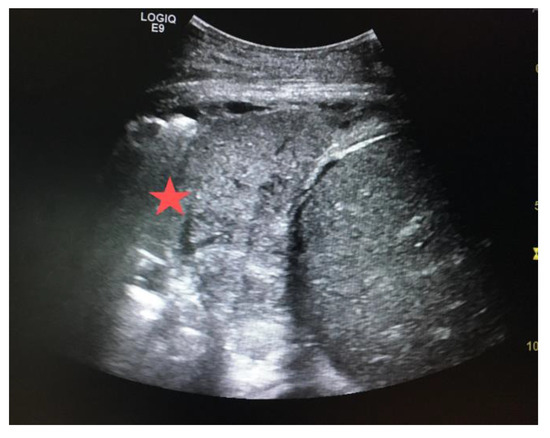

3.4.3. Hypovolemia